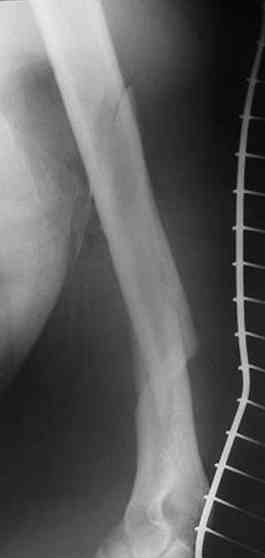

Несмотря на высокоэнергетический характер ранения, пуля не попала

непосредственно в кость, а прошла рядом. Таким образом, для бедренной

кости это ранение нельзя назватьв полном смысле этого слова

высокоэнергетическим. К сожалению, не видно выходное отверстие. В

любом случае, при таком переломе интрамедуллярный остеосинтез вполне

таком характере перелома привожу следующий случай. Пациент оперирован

на 5-е сутки (переведен из другого лечебного учреждения)после

сквозного пулевого ранения плеча и грудной клетки (непроникающее

ранение той же пулей). Выполнен минимально инвазивный остеосинтез

блокируемой метадиафизарной пластиной, повторная хирургическая

обработка ран плеча. Заживление всех ран первичное, сращение

наступило в обычные сроки.